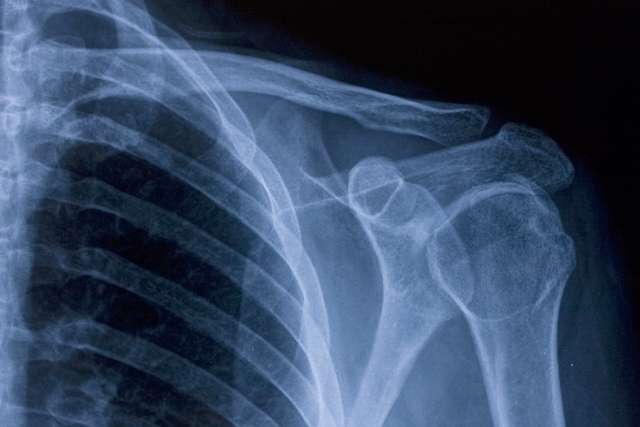

Shoulder X-ray.